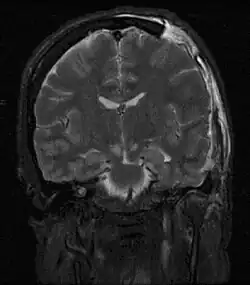

MRI showing injury due to brain herniation